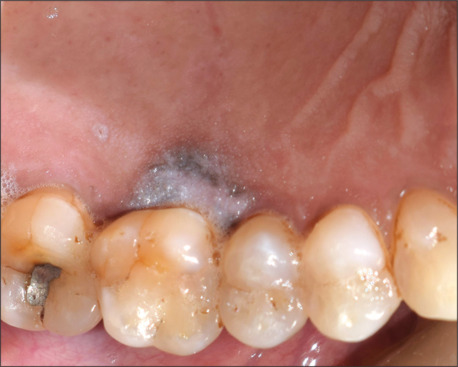

口腔白斑是一种常见的口腔潜在恶性疾病,如果不及时治疗,可能会发展为口腔鳞状细胞癌。虽然舌和颊粘膜是最常见的受累部位,但累及腭龈是相对罕见的。它通常与高复发率和更高的恶性转化倾向有关。手术切除病变被认为是金标准的治疗策略。本病例报告描述一例口腔白斑累及腭龈在一个71岁的男性没有有害的口腔习惯。病变采用手术切除治疗,缺损采用对侧腭龈游离龈移植物修复。虽然术后2年未见复发,但建议患者定期监测。

Oral leukoplakia is a frequently encountered oral potentially malignant disorder that, if left untreated, could progress to oral squamous cell carcinoma. Though the tongue and buccal mucosa are the most common sites to be affected, the involvement of palatal gingiva is relatively rare. It is usually associated with high recurrence rates and a higher tendency to undergo malignant transformation. Surgical excision of the lesion is considered the gold-standard treatment strategy. This case report describes a case of oral leukoplakia involving the palatal gingiva in a 71-year-old male having no deleterious oral habits. The lesion was treated using surgical excision, and the defect was repaired using a free gingival graft from the opposite palatal gingiva. Although no recurrence was noted till 2 years following surgery, the patient was advised to undergo regular monitoring.